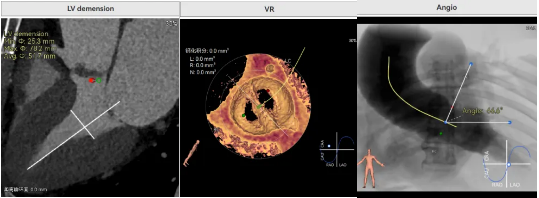

病例概览

患者病史 男性,74y, 因 “发现心脏瓣膜病 1 年,加重伴喘气半年” 入院。门诊检查显示主动脉瓣重度AS并伴轻-中度AR。患者基础疾病较多:胸腹主动脉多发穿透性溃疡、心功能III级等,手术指征明确,但风险极高。 术前CT LVOT- Annulus 倒梯形,对植入瓣膜有挤压位移风险,Annulus直径23.7mm,瓣叶增厚,钙化集中在无冠窦边缘。 左冠脉开口高度可,瓣叶不长、窦部空间较大,无冠脉风险;室间隔膜部较短,有一定PPI风险,心脏角度37.9°;心室较小,有一定循环崩溃风险,术前注意补液。 术前造影角度及入路:血管入路散在钙化、无迂曲;主动脉弓条件好、双侧股动脉直径大、右股穿刺点侧壁存在环形钙化 左右重合位:RAO 7° CAU 21° 右窦中心位:LAO2 1° CAU 1° 手术策略 20mm球囊预扩后植入AV26瓣膜,同时做好预防循环崩溃、传导阻滞的应急预案。 术中挑战 1)球囊预扩:20mm球囊预扩时无明显 “腰征”,但存在少量反流,提示瓣膜钙化与解剖结构对扩张的阻力不均 2)首次释放偏差:第一次定位释放时,瓣膜在 “开花” 过程中下滑约 3mm,工作位观察显示小弯侧瓣周漏较多(深度超过完全覆膜区),需二次调整。 3)二次精准定位:以猪尾导管为参照,将定位点调整至 “猪尾 - 2mm” 处,结合真实窦底深度(较深)重新释放,最终瓣膜位置稳定,瓣周漏显著减少。 术后即刻效果: 瓣膜形态良好,跨瓣压差从术前的 67mmHg 降至 6mmHg,且无明显瓣周漏,冠脉开口通畅; Commisural Alignment 术后即刻超声: Prostyle A®预装干瓣——助力临床最优化解决方案: √ 平衡的径向支撑力:特殊的解剖结构下位置形态良好,术后跨瓣压差大幅降低,血流动力学改善明显; √ 80%可回收设计:支持术中二次调整释放位置,保证精准释放; √ 平衡的收腰设计&Commissural Alignment设计: 为患者后期冠脉PCI保留了生命通道;